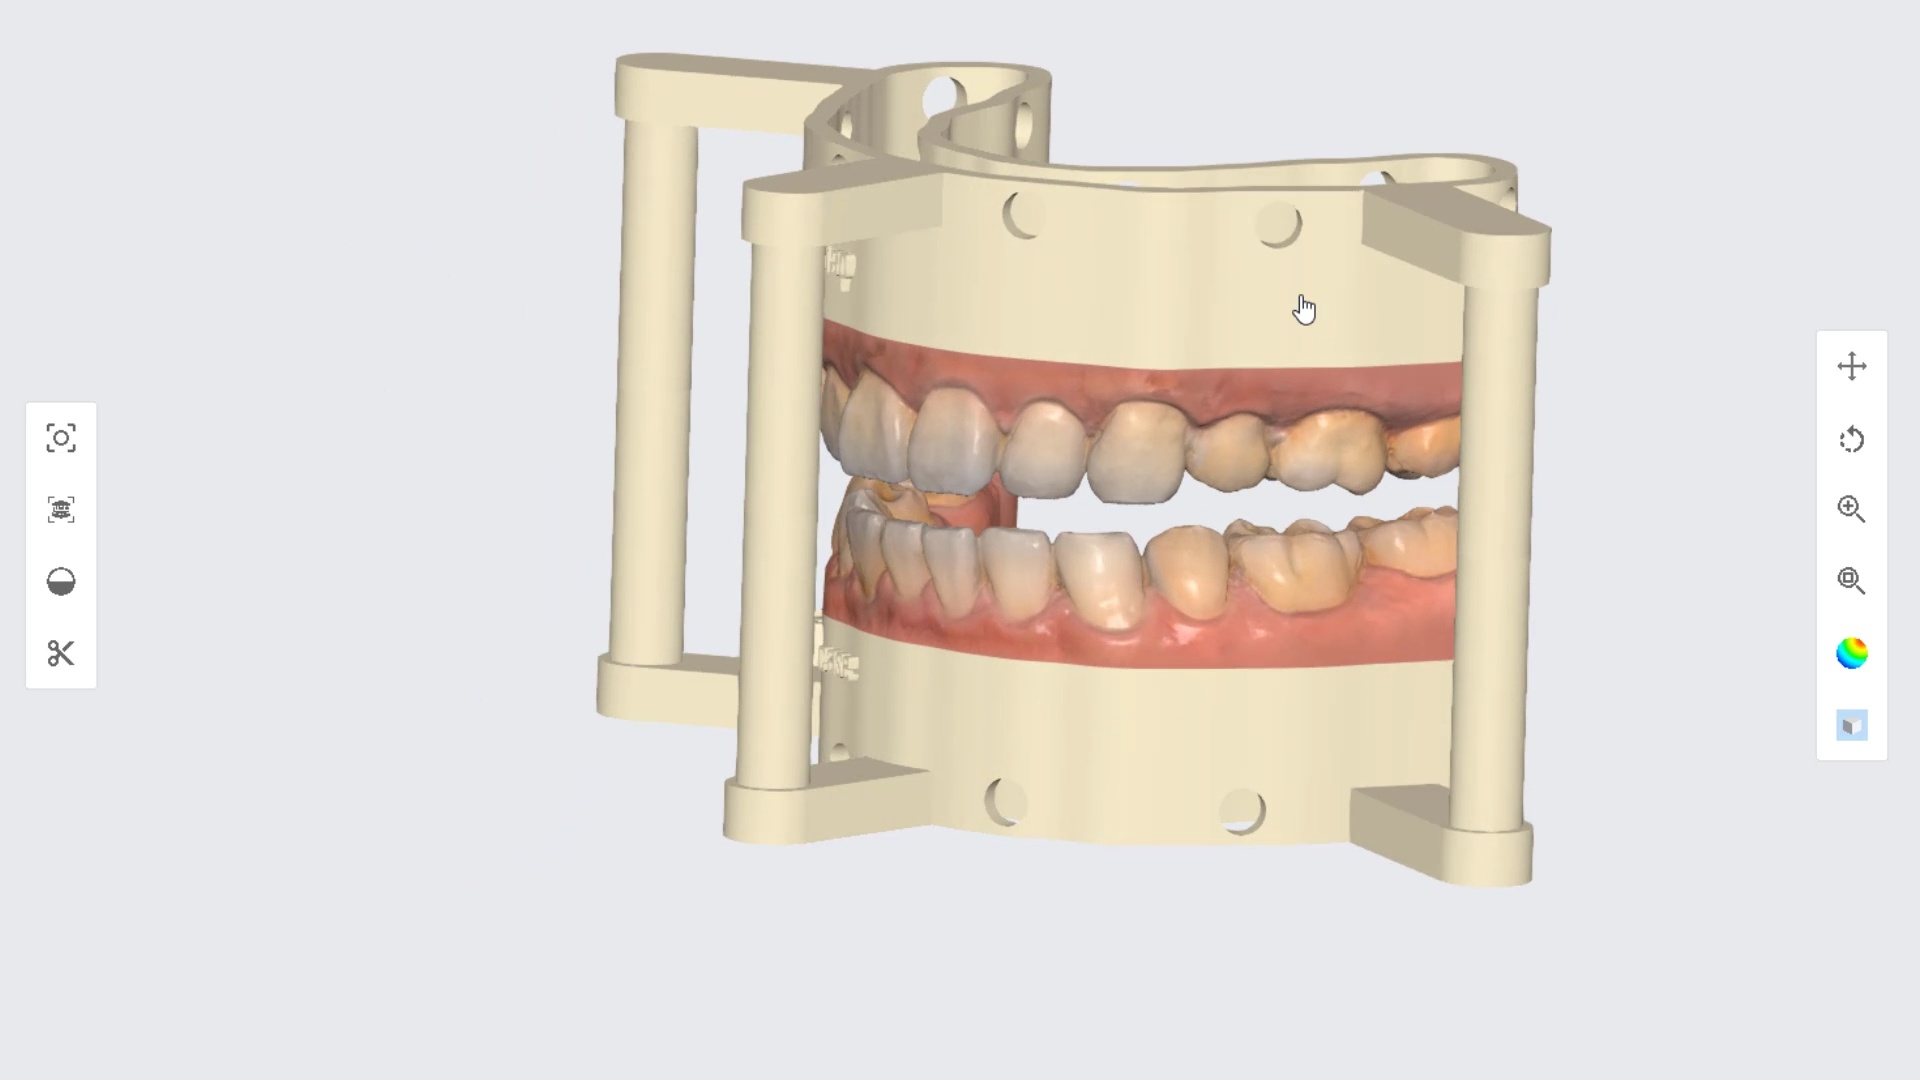

Full Mouth Rehab under Sedation

March 17, 2022the patient was sedated and intubated for the case so we could not keep track of the bite. Instead, we imaged all 30 prepared teeth and used medit compare […]

the patient was sedated and intubated for the case so we could not keep track of the bite. Instead, we imaged all 30 prepared teeth and used medit compare […]